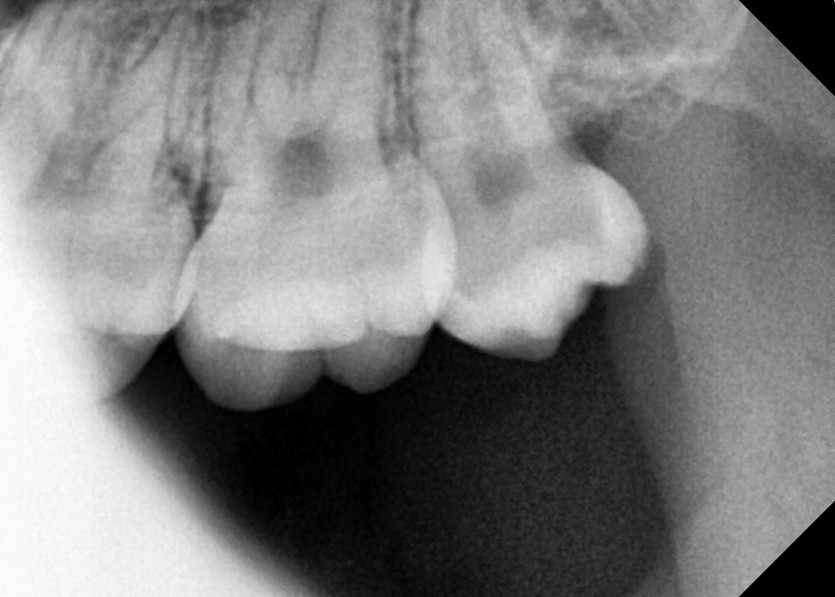

#18,28,38,48 사랑니 발치

구강 외과 전문의가 당일 발치했습니다.